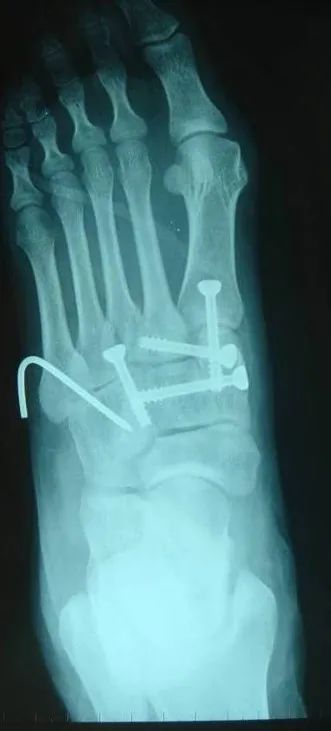

内固定选择1、克氏针:优点是手术简单、时间短、对周围组织损伤小,缺点是固定不坚强、复位丢失等情况时有发生。2、可吸收螺钉:优点是不需行二次手术取出内固定物,缺点是固定强度不及传统螺钉3、小螺钉系统:经典 --- 3.0mm、3.5mm、4.0mm4、空心螺钉:3.0mm、4.0mm、4.3mm 、4.5mm5、微型钢板:跨关节固定,对于严重的跖骨粉碎性骨折的患者,螺钉无法固定时,建议选择微型钢板桥接固定6、骑缝钉

根据三柱理论1、首先复位内侧柱并临时固定 2、再复位固定中间柱3、如外侧柱移位可能需双切口

手术从第一跖骨和内侧楔骨开始。首先直视下复位该关节,评价楔骨之间的稳定性,关节囊通常撕裂,但仍然需要掀开以充分显露关节,清除关节内的软组织和软骨碎片内侧柱稳定后,开始处理第二跖骨和中间楔骨。点式复位钳由第二跖骨基底部外侧远端斜向内侧楔骨内侧面的近端夹持,注意避免第二跖骨向下移位,发生复位不良。

若楔间关节仍不稳,可使用楔骨间螺钉;固定内侧两跖骨后,通常第三跖骨已经足够稳定,若仍未复位,可以参考第一跖骨固定方法固定。通过第二切口固定第4、5跖骨。可以使用克氏针固定。

Lisfranc损伤骨折复位标准:1、C形臂透视显示正、侧、斜位均为正常解剖复位2、如复位后第1、2跖骨基底间隙和内、中楔骨间隙<2mm,跖跗骨轴线<15°为近解剖复位,可以接受,超过这个范围的移位则无法接受3、复位好后,沿第一跖骨轴线向内侧楔骨逆行拧入一枚4.0mm皮质骨螺钉。螺钉由关节远侧1.5-2.0cm处进入,平行于足底或略向跖侧。

4、从内侧楔骨向第二跖骨置入一枚螺钉,重建韧带。螺钉自内侧楔骨近端的背侧置入,指向第二跖骨背侧皮质的下方,螺钉应通过4层皮质,确保对第二跖骨的双皮质固定

术后管理石膏固定4~6周;如果固定稳定,术后两周可开始功能锻炼,4~6周部分负重,六周后完全负重;术后6~8周可拔去克氏针,术后3~4月可取出螺钉。有些人主张若无症状出现,可无限期地留置螺钉于体内